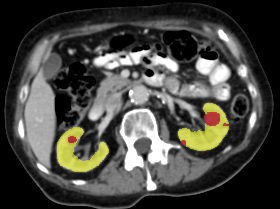

Refer to caption

(a) Input CT scan

(b) Annotations format 1

(c) Annotations format 2

Figure 2: Example illustrating the different annotation formats. Each subfigure shows the same axial section, with overlays depicting the annotations: (a) shows the axial CT section. (b) shows the annotations in format 1: parenchyma and kidney abnormalities as a single structure (yellow overlay). (c) shows the annotations in format 2: parenchyma (yellow overlay) and kidney abnormalities (red overlay) as different structures. All images have a window center of 60 HU and a window width of 360 HU.

This study utilized two annotation formats, format 1 and format 2, to store the annotations. Format 1 considers the kidney parenchyma and kidney abnormalities as a single class (see Figure 2(b)) while format 2 separates them into two classes (see Figure 2(c)).